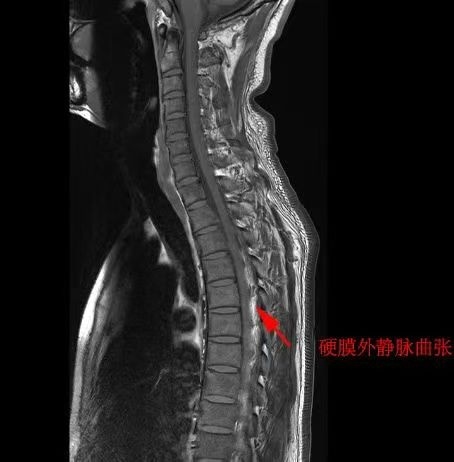

入院后,陈镇洲讲授团队速即为苏先生张开病因探查。胸椎磁共振成像(MRI)查验露出“椎管后缘静脉丛膨胀”,脑脊液漏导致静脉代偿性膨胀。脑脊液漏口常荫藏在脊柱椎管内,定位难度不小。通过精确的核素脑脊液扫描获胜定位了“罪魁首恶”——位于胸椎段的两个明确的脑脊液漏口。